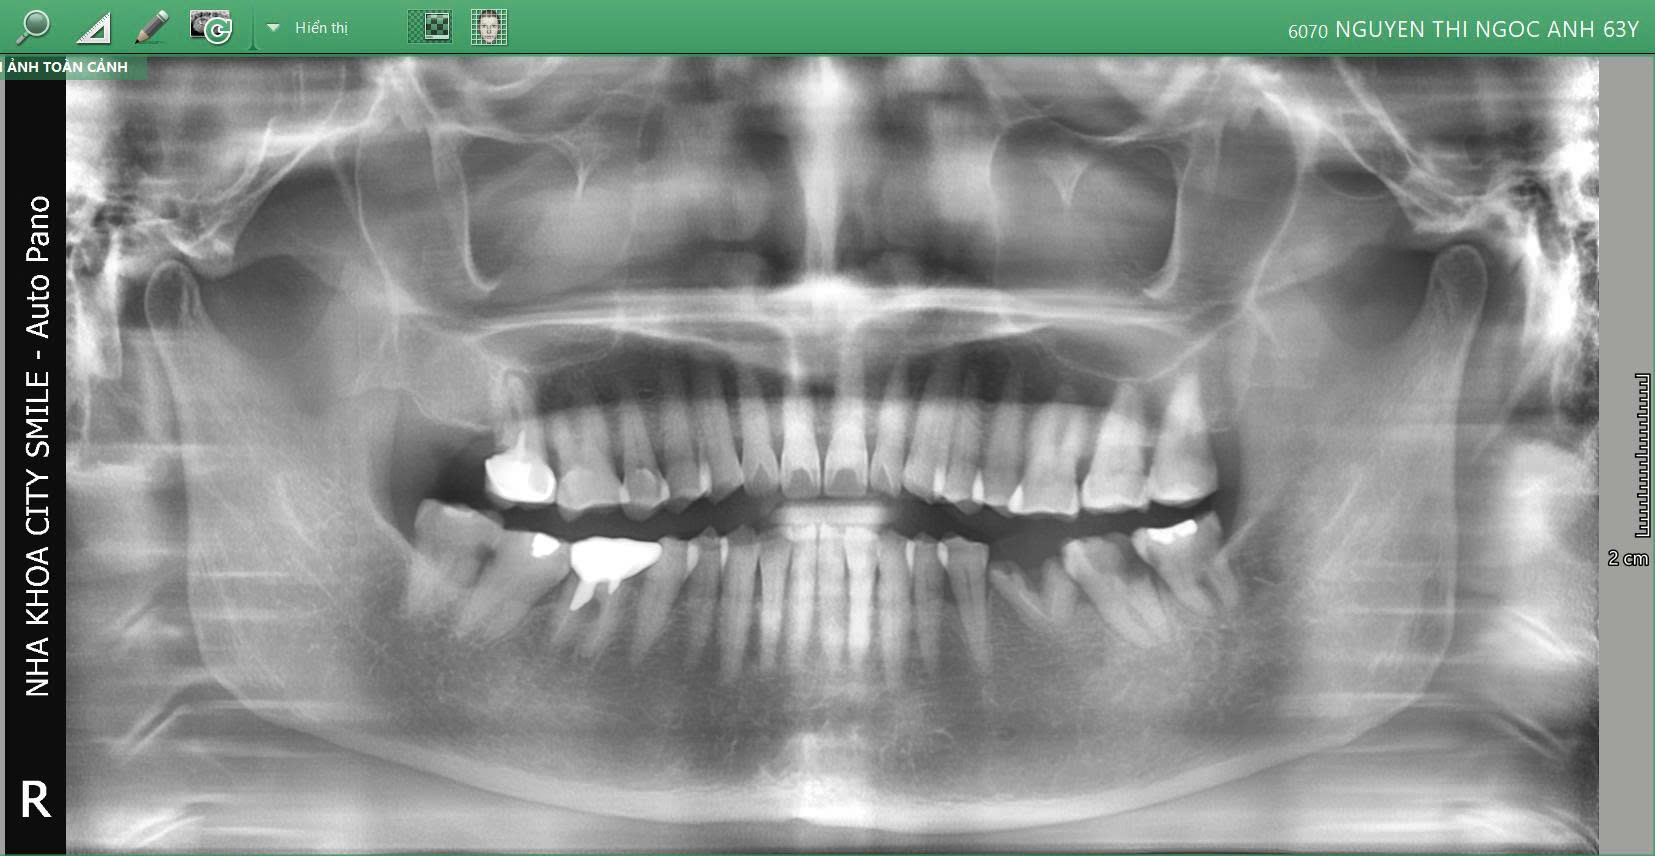

Cô Nguyễn Thị Ngọc Ánh – 63 tuổi đã đến City Smiles trong tình trạng đau nhức răng khôn và mất răng hàm dưới, gây khó khăn khi ăn nhai và ảnh hưởng sinh hoạt hàng ngày. Sau thăm khám toàn diện, phòng khám đã xây dựng phác đồ điều trị kết hợp Implant và nhổ răng khôn để giải quyết triệt để hai vấn đề này.

1. Tình trạng ban đầu

🔹 Răng 36: Mất răng lâu ngày, xương hàm bị tiêu nhiều → cần ghép xương trước khi đặt trụ Implant để đảm bảo độ vững ổn.

🔹 Răng khôn 48: Mọc lệch, gây đau nhói từng đợt, ảnh hưởng việc ăn nhai và giấc ngủ.

Đây là những tình trạng thường gặp ở người trưởng thành lớn tuổi khi không điều trị sớm.